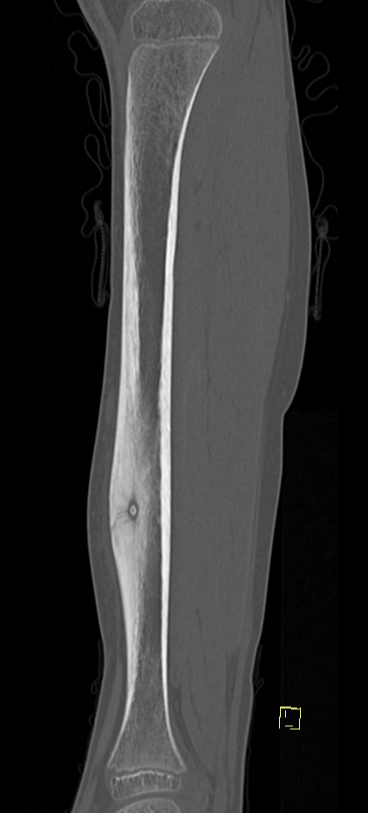

Osteoid osteoma